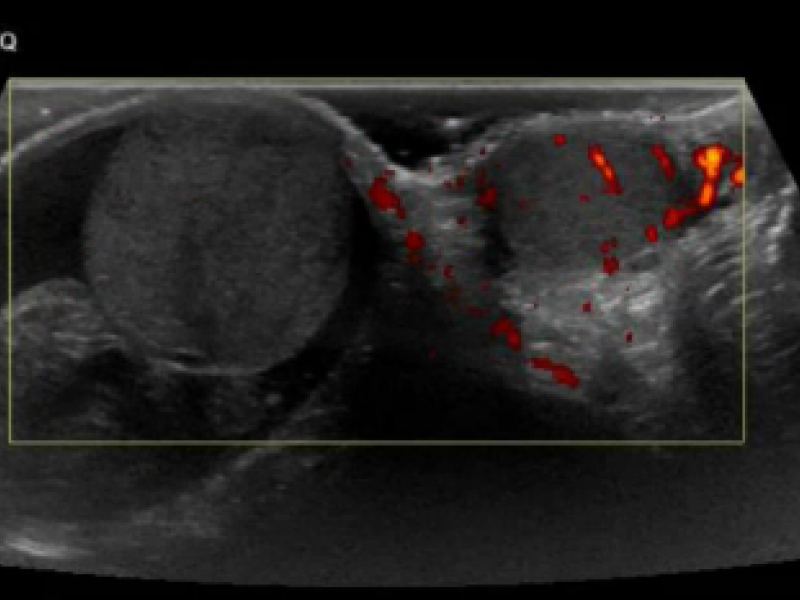

Advanced Cases and Content: Genital Pain

EM Daily

September 07 2021

11-year-old boy previously health who presents with